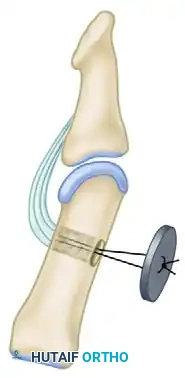

For Adults (Skeletal Maturity Achieved): Arthrodesis

- Expose the IP joint by elevating the extensor apparatus dorsally or through the existing midlateral approach.

- Denude the articular cartilage of the head of the proximal phalanx and the base of the distal phalanx down to bleeding subchondral bone using a rongeur or a small oscillating saw.

- Coapt the bony surfaces in approximately 15 degrees of flexion.

- Fix the joint securely using a retrograde crossed Kirschner wire (K-wire) technique or a headless compression screw.

For Children (Open Physes): Tenodesis

- To avoid iatrogenic injury to the open physis of the distal phalanx, an arthrodesis is contraindicated.

- Instead, perform a tenodesis of the distal FPL stump to the proximal phalanx.

- Suture the FPL stump to the periosteum or through drill holes in the proximal phalanx, securing the IP joint in 15 degrees of flexion. Alternatively, a pull-out button technique can be utilized for rigid temporary fixation while the tenodesis heals.